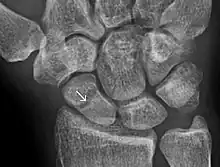

- Delayed union: healing times vary depending on the location of a fracture and the age of a patient. Delayed union is characterised by 'persistence of the fracture line and a scarcity or absence of callus formation' on x-ray. Healing is still occurring but at a much slower rate than normal.[9]